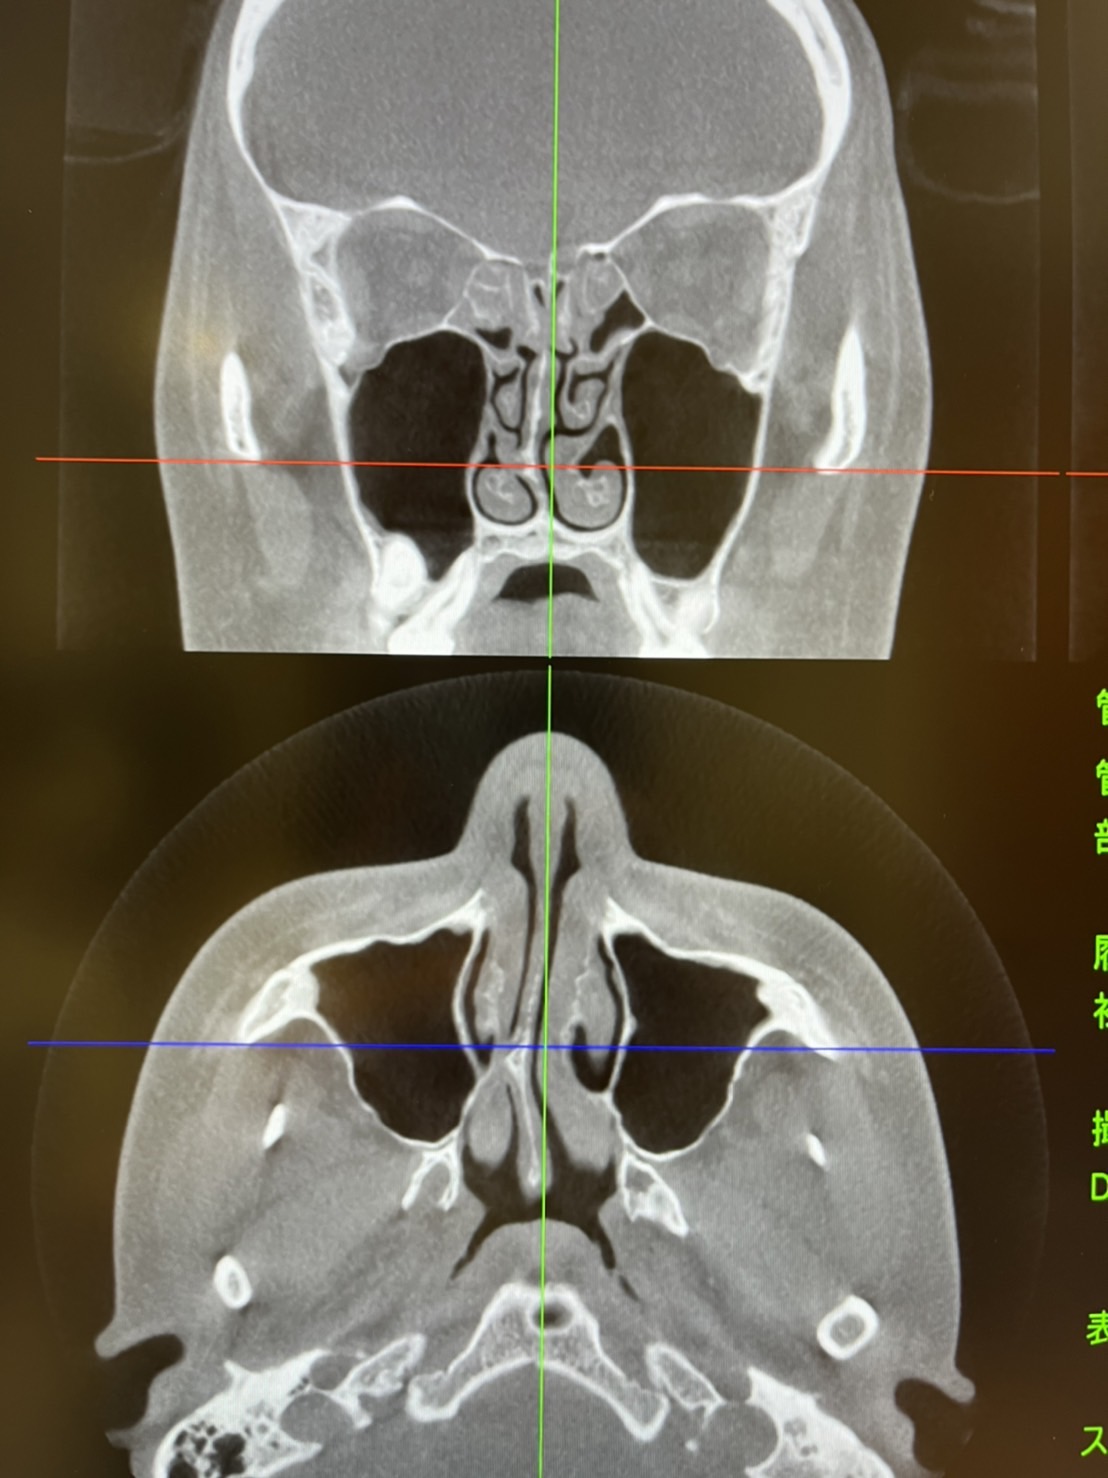

カテゴリー 日常 かすみがうら 投稿者 作成者: Kiyoshi 投稿日 2022/03/17 かすみがうら へのコメントはまだありません ここはいつも早くて日の出前に終わる。 華恋はずっと治らない鼻を 東京の医師を見つけ行ってみると 手術になった。 怖くてやらない医者が多いんだろうな。